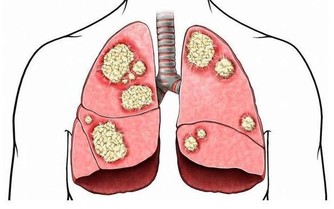

刺梨聽過這名字的人想必都很少,其實它屬於薔薇科植物繅絲花的果實,又名茨梨,被稱為天然維C之王,富含的多種微量元素,可促進體內新陳代謝,排出卵巢中的毒素廢物。

女人如果補充了足夠的維生素,患卵巢癌的機率能降低到一半,每天用3-5顆刺梨幹泡水喝,輕鬆讓卵巢恢復年輕活力。